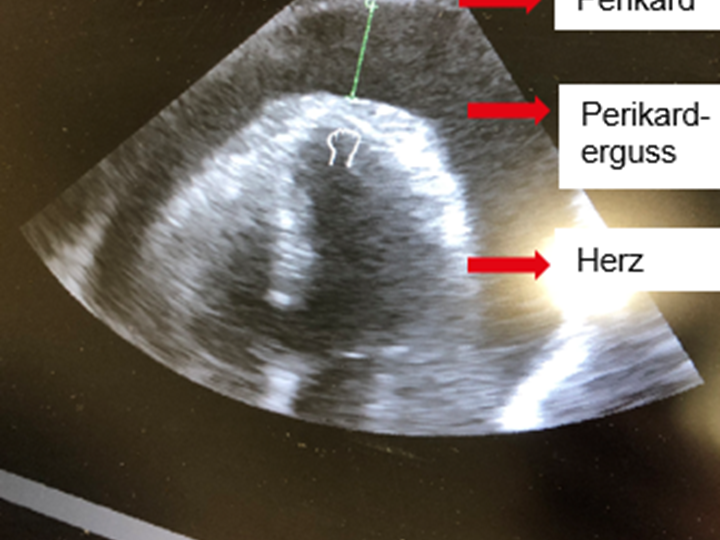

Im NIBD rechtsseitig ist mittlerweile kein Blutdruck messbar, in der IBP links radial ein erster Wert von 50/25. Es werden nun mehrmals Norboli verabreicht, sowie der Verdacht auf Aortendissektion in den Raum gestellt. Ein orientierendes Herzecho durchgeführt, parallel der Herzchirurg verständigt.

Es zeigt sich also ein ausgeprägter Perikarderguss (Flüssigkeitsansammlung innerhalb des Herzbeutels).

Wie erwähnt ist eine präklinische Diagnose einer A-Dissektion nahezu unmöglich. Auch wenn immer häufiger in den primären Sonderrettungsmitteln ein Sonogerät zur Verfügung steht, sind kann keine sichere Diagnose erreicht werden. Eine suprasternal darstellbare Dissektionsmembran ist selten und schwierig darstellbar (suprasternal), häufig sind außerdem Artefakte. Aorteninsuffizienz kann sehr unspezifisch sein, hingegen ist eine Perikardtamponade ein sehr deutlicher, wenn auch wieder seltener Hinweis auf eine Dissektion.